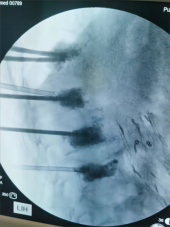

8. 机器人导航辅助下脊柱侧弯矫正技术

脊柱侧弯是一种复杂的脊柱三维畸形,其中以青少年特发性脊柱侧凸最常见。性爱视频

在浦口地区率先开展机器人导航辅助下脊柱侧弯矫正术,实现了脊柱侧弯手术准确、微创、智能化的突破,获得了良好的效果。还有老年人退变性侧弯,机器人亦可精准置入困难椎弓根螺钉,误差只有0.3mm。